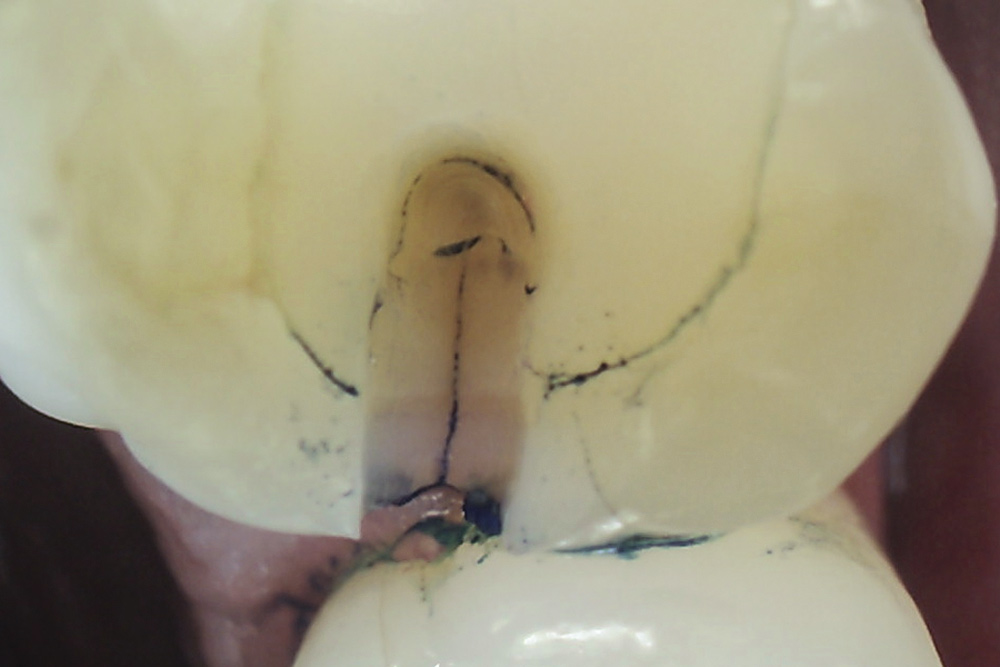

Fig 10. Stained asymptomatic enamel marginal ridge crack (arrows) of a maxillary right first molar extending to the existing restoration (mesio-occlusal view).

Figure 10

Fig 11. Exploratory fissurotomy and methylene blue dye staining revealing an underlying deep dentin crack in tooth shown in Fig 10.

Figure 11

Whenever asymptomatic enamel cracks extend into dentin and cannot be eliminated by minimally invasive fissurotomy without causing additional damage to the tooth and underlying structures, protection is recommended to minimize their propagation (Figure 10 and Figure 11).3,14 Occlusal coverage restorations have demonstrated greater overall success in the treatment of symptomatic cracks by immobilizing the cracked segments that move on loading, with better prognosis seen when more conservative restorations are used.27,28 Although this might still be controversial, from a biomechanical perspective these principles can conceptually apply to the treatment of asymptomatic dentin cracks. Occlusal coverage restorations have been recommended to protect asymptomatic teeth with existing dentin cracks from further cracking (Figure 12).2,3,9,29